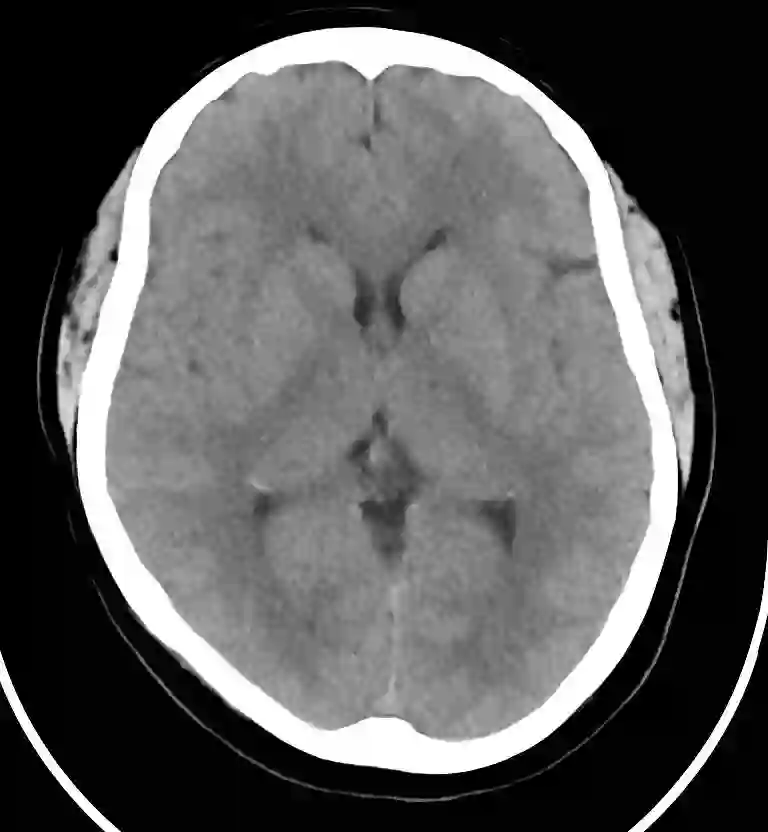

GE 医疗产品线中首个融入英伟达 AI 系统的将会是 Revolution 系列的新型 CT 系统。在加入 AI 系统后,Revolution Frontier CT 的图像处理速度实现了翻倍,将可以提供更快速的肝脏和肾脏检测,减少病人的负担。

图丨 Revolution CT 的成像